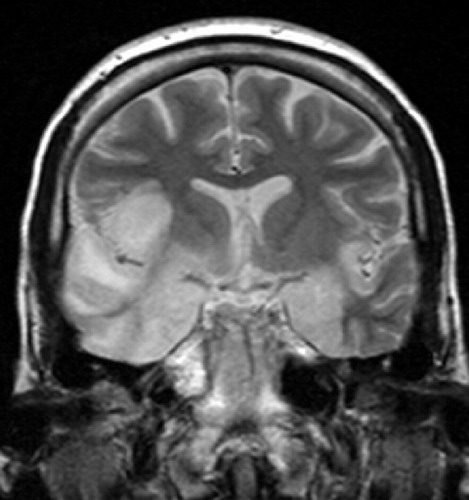

Encephalitis

The other two more general kinds of ‘encephalitis’ that you must be aware of includes ‘Japanese encephalitis’ and ‘tick-borne encephalitis’. The word ‘encephalitis’ means irritation of the brain and is generally caused by viruses. ‘Japanese encephalitis’ is caused by a flavivirus (JEV) that is spread by bite of mosquitoes which are carrying the virus in them. Mosquitoes which belong to Culex category are the most dangerous. ‘Tickborne’ encephalitis is also caused by a flavi-virus (TBEV) which is spread from the bite of a contaminated tick. Ixodes class tick is the most dangerous in its class.